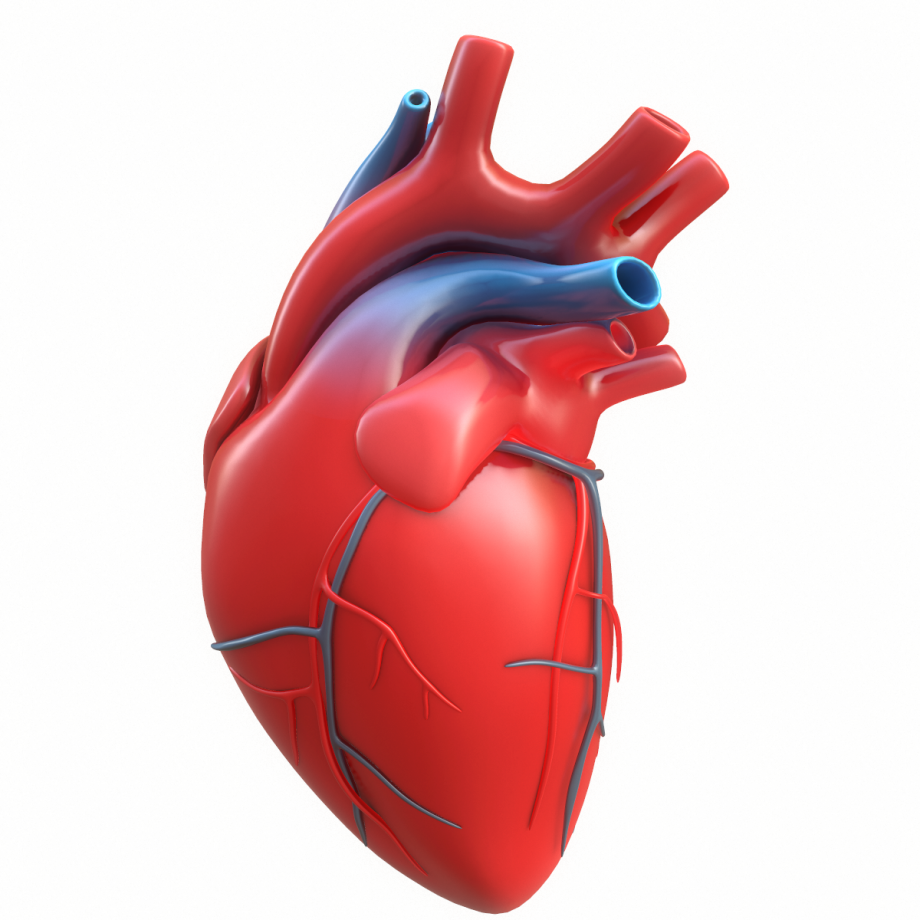

Анатомия здорового сердца: фотографии и иллюстрации